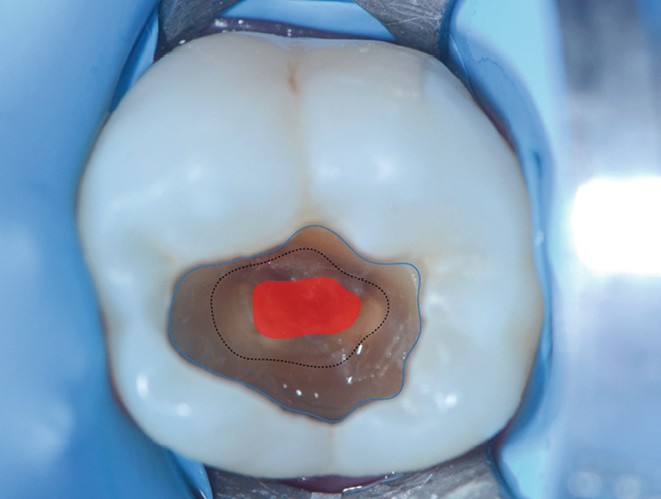

Le curetage total consiste à éliminer l’ensemble de la dentine cliniquement altérée (dentine nécrosée, infectée et affectée (fig. 1)) jusqu’à l’obtention d’un fond de cavité dur et visuellement sain (fig. 2). Cette approche repose sur un objectif clair : réduire au maximum la charge bactérienne et offrir un fond de cavité permettant un collage idéal. Dans les lésions profondes, elle expose toutefois à un risque d’effraction pulpaire [2] (fig. 3). Ce risque est aujourd’hui mieux accepté grâce aux progrès des biomatériaux de coiffage pulpaire, notamment les silicates de calcium (fig. 4), qui permettent une cicatrisation pulpaire prédictible lorsque le diagnostic est favorable, le protocole rigoureux et l’hémostase contrôlée. En cas d’effraction pulpaire, cette technique permet en outre l’évaluation visuelle directe de la pulpe (aspect, couleur, saignement). Le protocole clinique impose d’être sous champ opératoire et nécessite un plateau technique adapté.